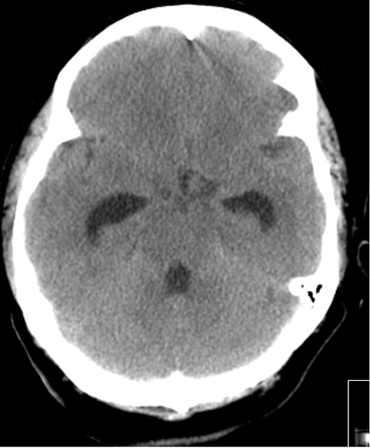

Acute hydrocephalus (HCP) occurs in 15% to 20% of patients during the first 72 hours and is an obstructive HCP.[11][12][176] Its occurrence is related to presence of intraventricular blood and, to a lesser extent, thick cisternal blood collection.[176][177] The mortality rate in subarachnoid hemorrhage (SAH) patients with HCP is higher than in those without it.[176]

In patients with aneurysmal SAH and acute symptomatic hydrocephalus, urgent cerebrospinal fluid (CSF) diversion (external ventricular drain [EVD] and/or lumbar drainage) should be performed.[37] The use of prophylactic antibiotics with EVD is not established but is commonly adopted.[59] The optimum modes of CSF drainage (intermittent vs. continuous), EVD weaning (rapid vs. gradual), and EVD wean timing (following aneurysm securement vs. time of vasospasm risk) are uncertain.[7][112][178] It is unclear whether microsurgical fenestration of the lamina terminalis during surgical clipping of the aneurysm protects against the need for a permanent shunt in patients with hydrocephalus.[179][Figure caption and citation for the preceding image starts]: Communicating hydrocephalus in the setting of subarachnoid hemorrhage; note dilation of fourth and temporal horns of lateral ventriclesCourtesy of Dr Salah Keyrouz; used with permission [Citation ends].Communicating hydrocephalus in the setting of subarachnoid hemorrhage; note dilation of fourth and temporal horns of lateral ventricles